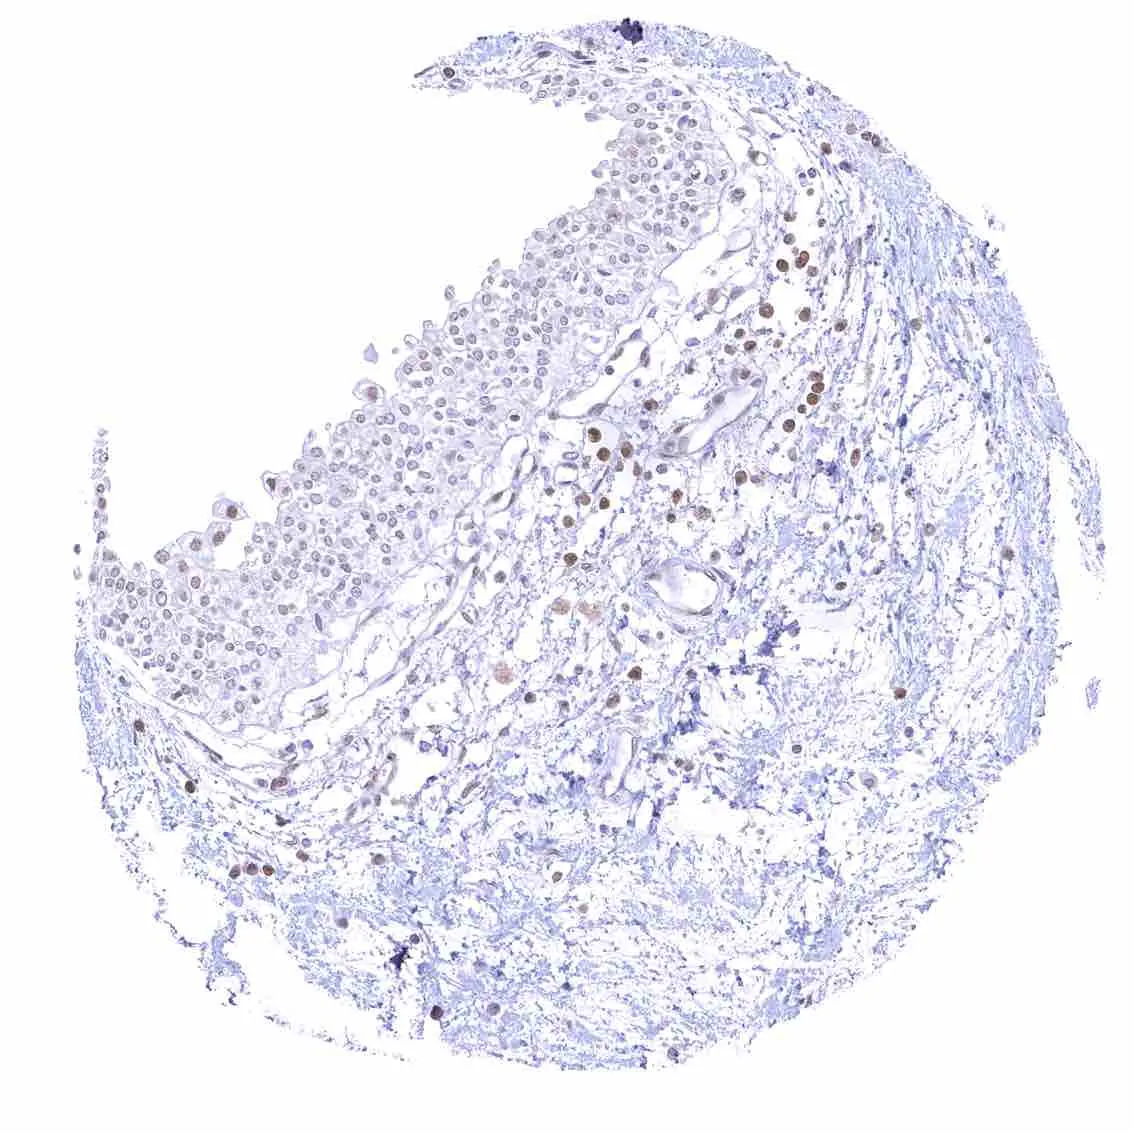

Uterus, endocervix – Nuclear p27 staining is variable in the endocervix. It is positive in all epithelial cells in this sample.

Uterus, endocervix